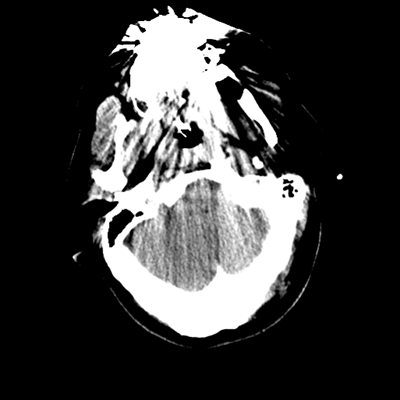

The patient goes down to CT. The following images are obtained. The subdural fluid collection is stable, as is the ventricular caliber.

Starting with the non-contrast head CT, we can appreciate that there's actually not much residual subarachnoid blood at all; it's essentially all resorbed already (and cleared through the EVD). The ventricular caliber is stable. With the CTA head (for convenience's sake, the MIPs were shown), it's subtle, but we can see that the PCAs on each side are not as smooth and regular. The right MCA, starting at the bifurcation, also becomes narrower. This is [radiographic] vasospasm. Now, looking at the CT perfusion-- specifically, the Tmax (MTT) map that were selected-- there's clearly some abnormality within the bilateral cerebellar hemispheres and occipital lobes. Not a lot, but it's there. Delving further into this map, we can appreciate that the areas of abnormality are mainly green, signifying that these areas have Tmax > 6 seconds. This is the threshold that is specific, not sensitive, for vasospasm.

Putting this all together, we have thus identified radiographic vasospasm with the vessel imaging, with perfusion abnormalities that are concordant with it. Does the area of vasospasm and hypoperfusion correlate with the patient's clinical exam?

Yes! It does. The patient had a decline in level of consciousness with diffuse loss of motor function. This does correlate to the basilar territory. (Alternatively, bilateral MCA vasospasm could also be responsible, reminding us that a decline in consciousness could technically be focal/multifocal.) Thus, we can say that this patient does have clinical vasospasm. Whether this will develop into irreversible DCI remains to be seen; at least, the non-contrast head CT and the other portions of the CT perfusion (not shown) currently don't [yet] suggest infarction.